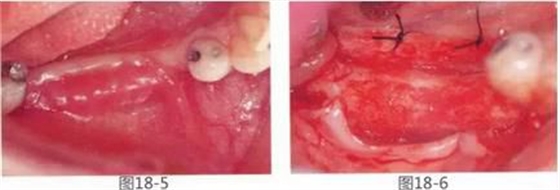

圖18-5 術(shù)后1個月的狀態(tài)??梢钥吹礁材ぢ冻?。

圖18-6 術(shù)后月1年。獲得充分寬度的牙槽嵴。